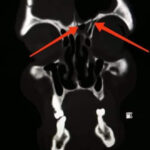

وأوضح مدير الهيئة الدكتور إسكندر عمار في تصريح لمراسلة سانا أنه تم قبول المريض ومتابعته في شعبة الجراحة العصبية، وبعد إجراء الاستقصاءات الشعاعية تبين وجود كسر قاعدة أمامية يسرى على مستوى الجدار الخلفي للجيب الجبهي ويمتد باتجاه الصفيحة الغربالية.

بدوره أوضح رئيس قسم أمراض الرأس والعنق وجراحتها الدكتور محمد خليل اختصاصي الأذنية أنها المرة الأولى التي تجرى فيها عملية نوعية بالتعاون بين الشعبة الأذنية والجراحة التنظيرية وشعبة الجراحة العصبية في المشفى، وذلك بعد تحديد مكان الكسور، ووضع خطة لمعالجتها ليتم التدخل تنظيرياً على منطقة النز والتدخل الخارجي على منطقة الكسر بالجدار الخلفي للصفيحة أو للجيب الجبهي.